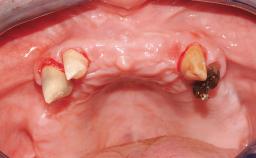

| Case Type | Single-Tooth Space |

| Jaw | Maxilla |

| Area | Anterior |

| # of Teeth | 1 |